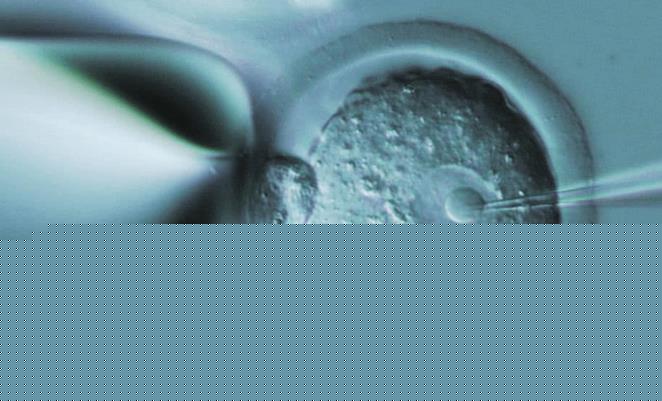

生化妊娠是指发生在妊娠5周内的早期流产,特点是HCG阳性(25mIU/mL),超声检查看不到孕囊。生化妊娠与胚胎停育对患者来说,都属于一次失败的妊娠,但他们并不是一回事。

生化妊娠大致可以理解为精子和卵子受精了,迈出了孕育生命的第一步。因为受精卵着床后第6天即开始产生少量的HCG,一般排卵后8天可以从外周血中测出相应数值。但这时的HCG(+)的数值是没有临床意义的。这时测出的妊娠,无法判别妊娠的部位、也无法预知它的前途。

2、在孕5周时,B超下可以看到小的胎囊,或可见胎芽,确定宫内妊娠,这时的妊娠才可以称为临床妊娠。但这时看不到胎心;

3、孕6-7周时,B超下胎囊清晰可见,并可见胎芽及胎心搏动。